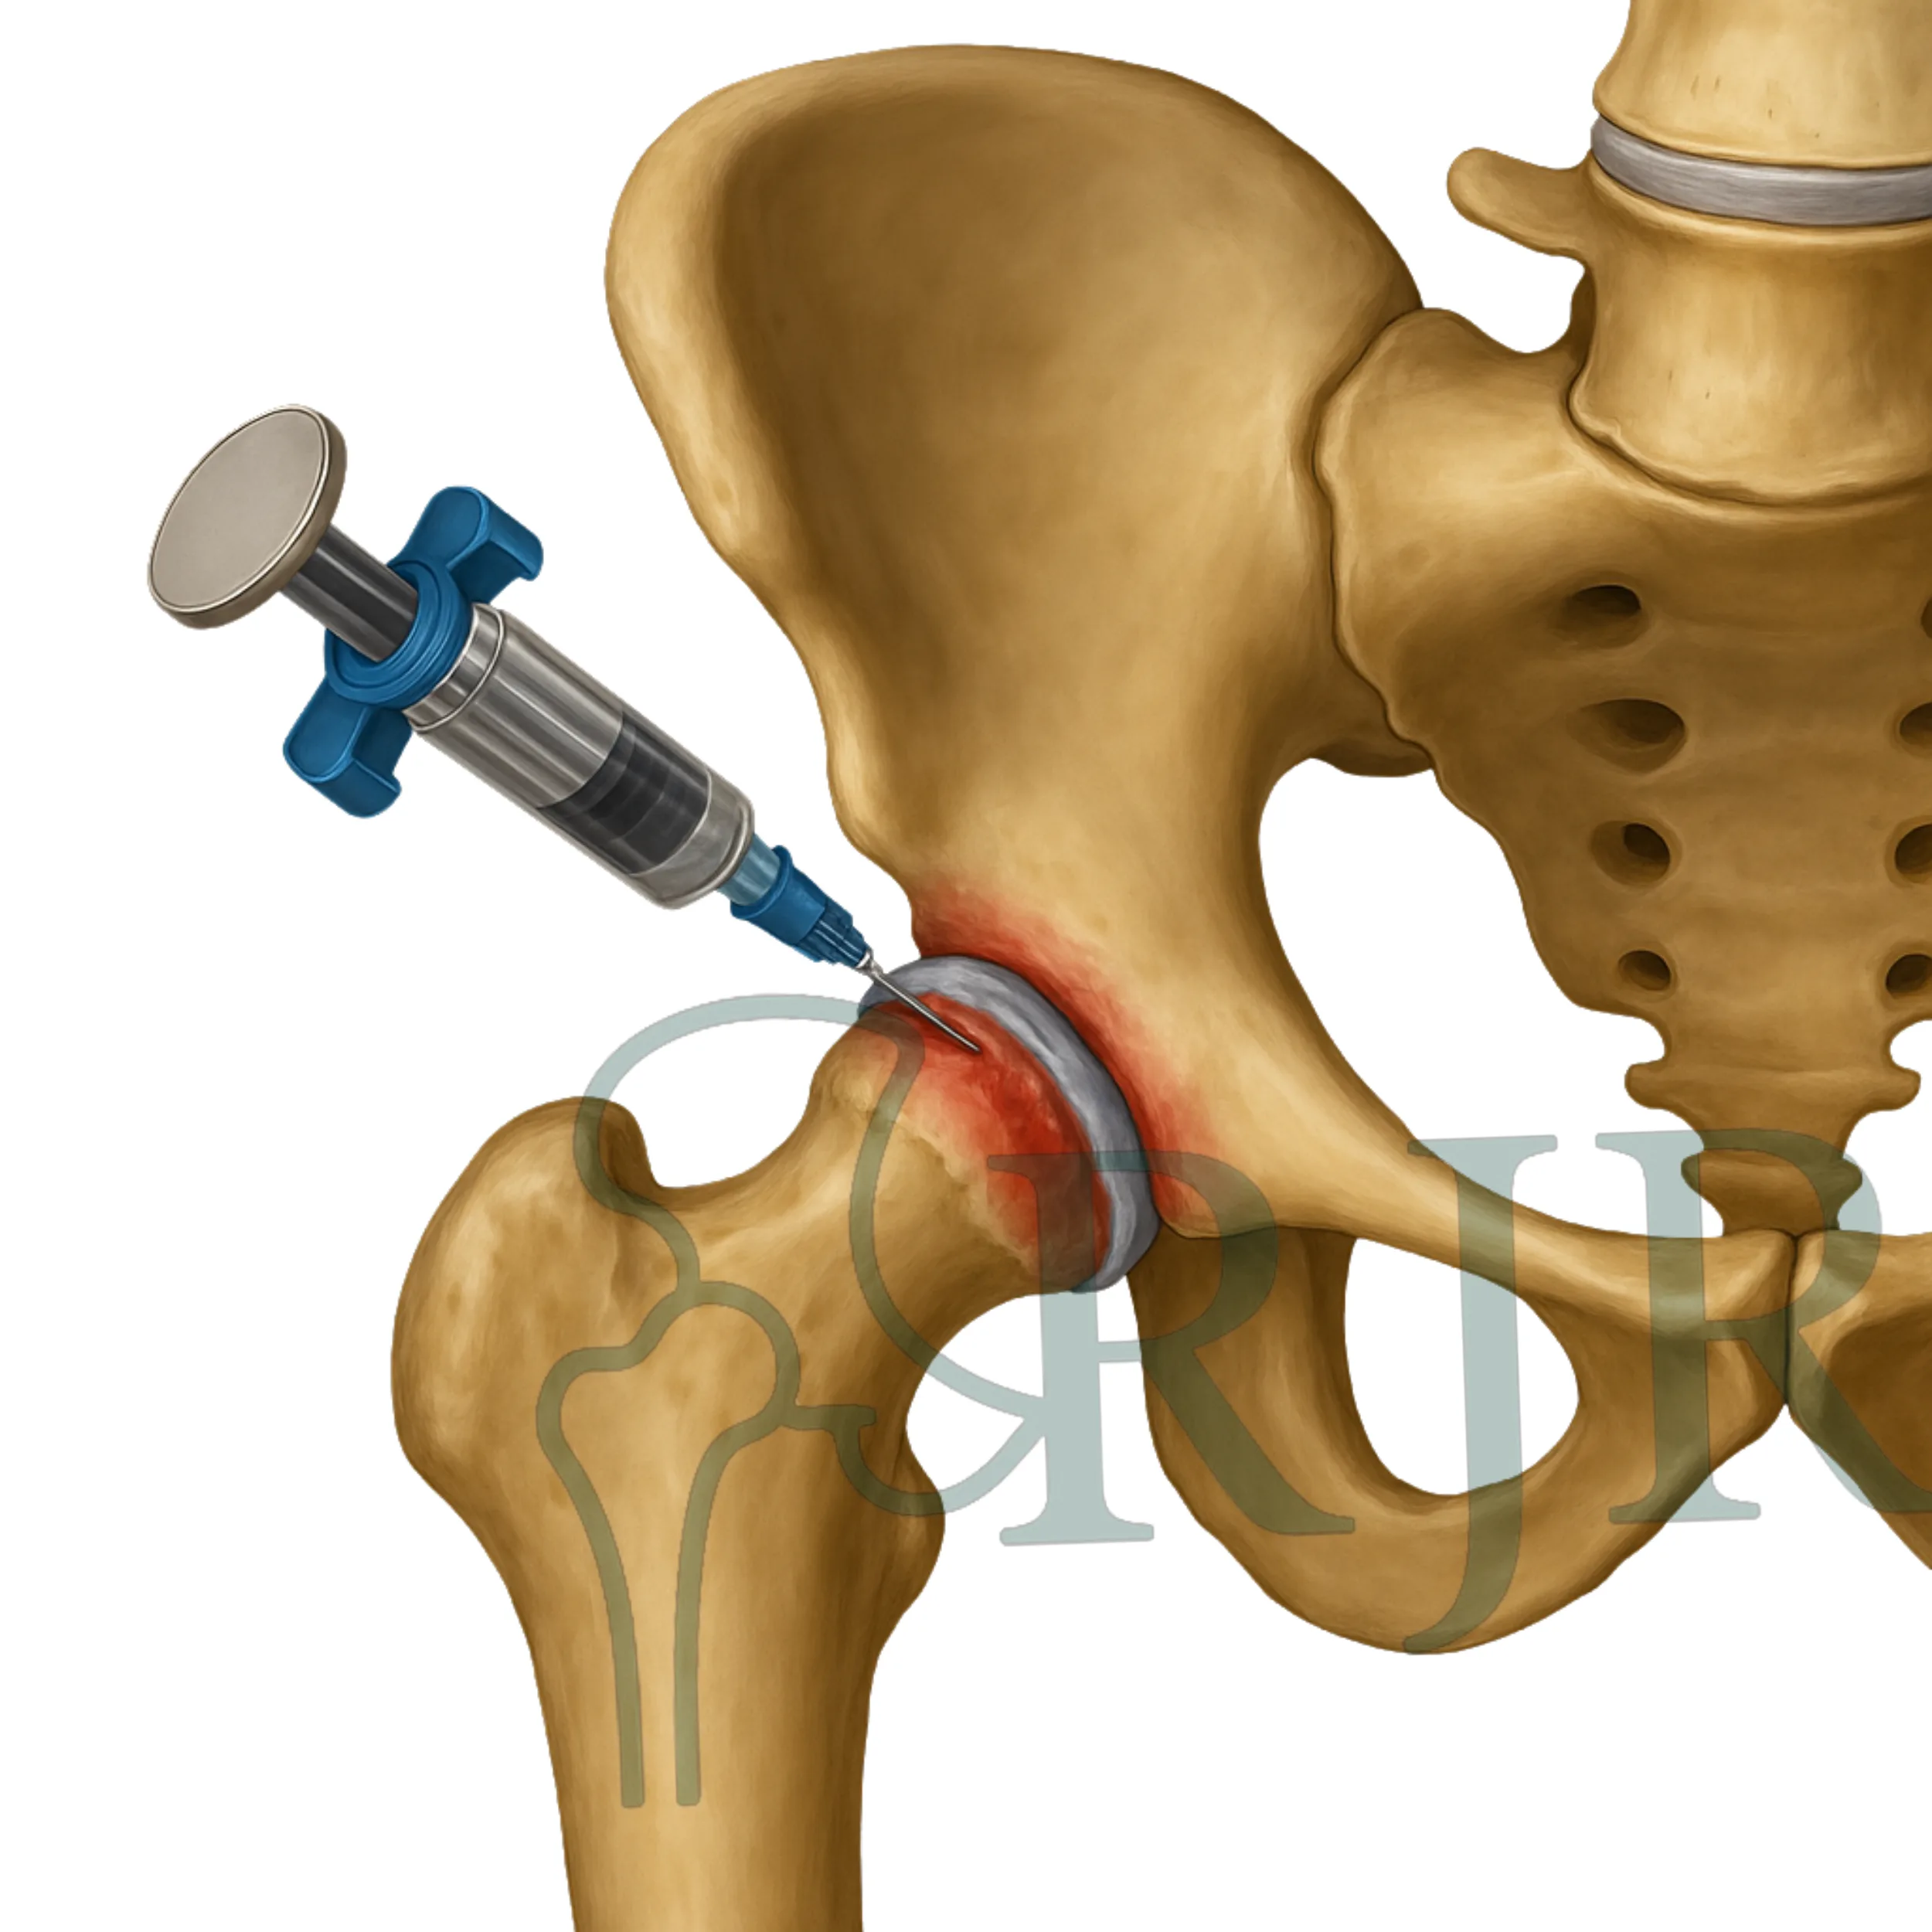

Infiltrações

Procedimento minimamente invasivo para alívio da dor e controle da inflamação, focado em promover conforto imediato.